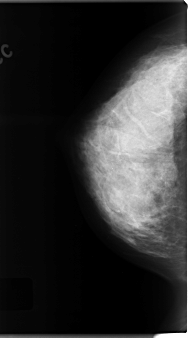

C_0120_1.RIGHT_MLO

RIGHT_CC LINES 4720 PIXELS_PER_LINE 2632 BITS_PER_PIXEL 12 RESOLUTION 50 NON_OVERLAY

RIGHT_MLO LINES 4760 PIXELS_PER_LINE 2464 BITS_PER_PIXEL 12 RESOLUTION 50 NON_OVERLAY